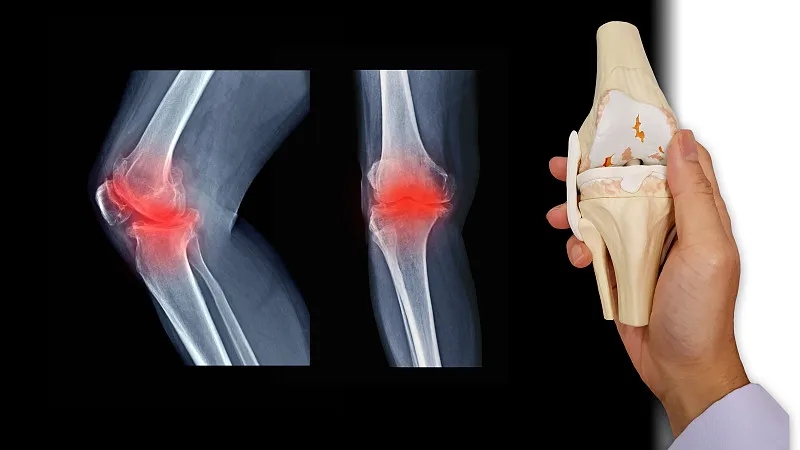

關(guān)節(jié)炎是一個(gè)通用術(shù)語,表示關(guān)節(jié)發(fā)炎。骨關(guān)節(jié)炎,俗稱磨損性關(guān)節(jié)炎,是最常見的關(guān)節(jié)炎類型。它與關(guān)節(jié)軟骨的破壞有關(guān),并且?guī)缀蹩梢园l(fā)生在身體的任何關(guān)節(jié)中。它通常發(fā)生在臀部、膝蓋和脊柱的負(fù)重關(guān)節(jié)中。它還會影響手指、拇指、頸部和大腳趾。

骨關(guān)節(jié)炎導(dǎo)致關(guān)節(jié)中的軟骨變硬并失去彈性,使其更容易受到損傷。隨著時(shí)間的推移,軟骨可能會在某些區(qū)域磨損,從而大大降低其作為減震器的能力。隨著軟骨退化,肌腱和韌帶伸展,引起疼痛。如果情況惡化,骨頭可能會相互摩擦。

如何診斷骨關(guān)節(jié)炎?

您的醫(yī)生可能會使用X光檢查來幫助確認(rèn)診斷并確保您沒有其他類型的關(guān)節(jié)炎。X 射線顯示發(fā)生了多少關(guān)節(jié)損傷。如果X射線結(jié)果不能明確指出關(guān)節(jié)炎或其他疾病,則可能需要進(jìn)行MRI以更好地觀察關(guān)節(jié)和周圍組織。